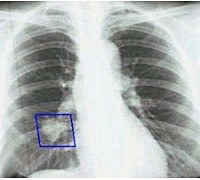

В обязательном порядке всем больным проводится двухпроекционная рентгенография легких. Рентгенпризнаки центрального рака легкого представлены наличием шаровидного узла в корне легкого и расширением его тени, ателектазом, обтурационной эмфиземой, усилением легочного рисунка в зоне корня. Линейная томография корня легкого помогает уточнить размер и локализацию опухоли. КТ легких информативно для оценки взаимоотношения опухоли с сосудами легких и структурами средостения.